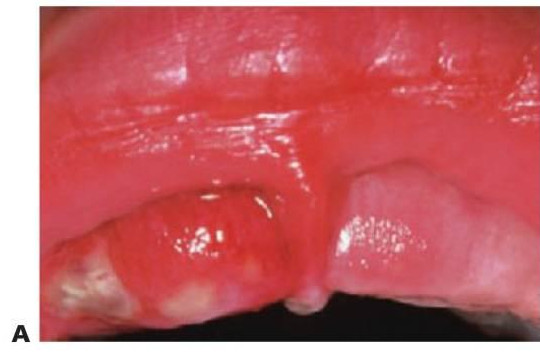

Las infecciones de la fosa canina del maxilar suelen producirse por grampositivos o bacterias anaerobias facultativas (fig. 8.1 A), pero pueden diagnosticarse de forma errónea como una celulitis periorbitaria, que se suele producir por Haemophilus influenzae o Staphylococcus aureus de diseminación hemática. La diseminación posterior puede llevar a una trombosis del seno cavernoso y a un absceso cerebral.

- Drenaje de pus. Si se ha retrasado el diagnóstico del tratamiento adecuado de una infección en la mandíbula y la inflamación ha cruzado la línea media, o bien existe una inflamación en el suelo de la boca, se debe considerar la realización de un drenaje extraoral de entrada-salida (fig. 8.1B, C). Si se eleva un colgajo, se debe eliminar todo el tejido de granulación e irrigar la zona minuciosamente. Los colgajos han de aposicionarse y suturarse sin ejercer mucha tensión con las suturas. Por último, los niños toleran mejor los drenajes flexibles blandos que los tubos corrugados.